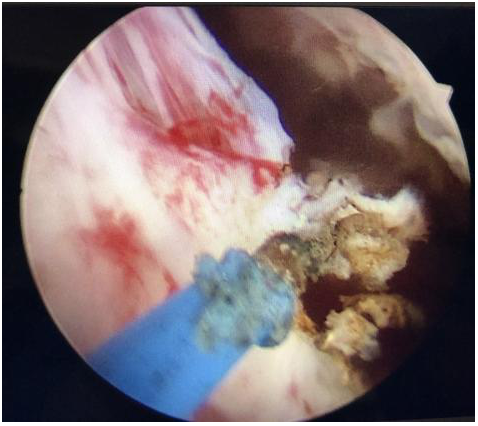

剜除后的效果